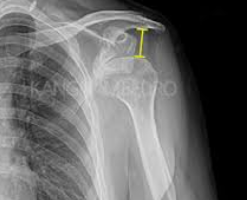

어깨탈구는 어깨 관절이 정상적인 위치에서 벗어나는 상태를 말합니다. 이는 스포츠 활동 중에 발생할 수도 있고, 갑작스러운 충격이나 부상으로 인해 발생할 수도 있습니다. 어깨탈구가 발생하면, 통증과 함께 어깨의 움직임이 제한될 수 있으며, 즉각적인 치료가 필요합니다.

치료 방법은 탈구의 정도와 환자의 상태에 따라 다를 수 있지만, 일반적으로 다음과 같은 절차를 따릅니다:

1. 긴급 처치: 탈구가 발생한 직후에는 어깨를 움직이지 않도록 고정하고, 얼음찜질을 통해 붓기와 통증을 줄입니다.

2. 정복: 의사는 부드럽게 어깨 관절을 원래의 위치로 돌려놓는 정복술을 시행할 수 있습니다. 이 과정은 통증을 수반할 수 있으므로, 때때로 진통제나 마취가 필요할 수 있습니다.

3. 재활: 정복 후에는 어깨의 안정성을 회복하고 근육을 강화하기 위한 재활 운동이 필요합니다. 물리치료사의 지도 하에 진행되는 것이 좋습니다.

4. 수술: 반복적인 탈구나 관절의 손상이 심각한 경우에는 수술적 치료가 필요할 수 있습니다.

어깨탈구는 적절한 치료와 관리를 통해 회복이 가능하지만, 재발 방지를 위해서는 예방이 중요합니다. 스포츠 활동 전에 충분한 준비 운동을 하고, 어깨 주변 근육을 강화하는 운동을 꾸준히 하는 것이 도움이 됩니다.

어깨탈구에 대한 자세한 치료 방법과 재활 과정은 전문의와 상담을 통해 개인의 상태에 맞는 최적의 방법을 찾는 것이 중요합니다. 만약 어깨에 이상을 느낀다면, 즉시 전문의와 상담하여 적절한 조치를 취해야 합니다.